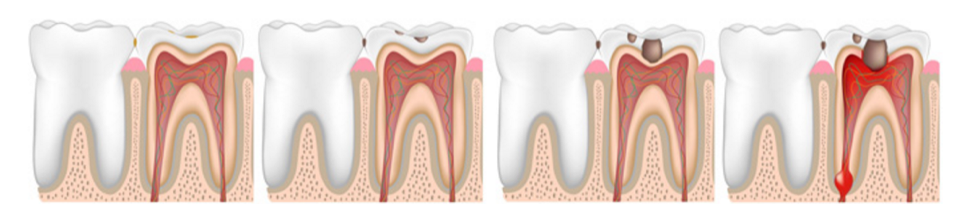

Wanneer bacteriën van een diepe cariës (gaatje) de zenuw en het bloedvat van de tand of kies bereiken, zullen deze ontsteken. Een ontstoken zenuw kan u herkennen aan volgende klachten: pijn bij het eten of drinken, gevoeligheid bij koud en warm, kloppend gevoel,… Door de ontsteking zal de zenuw uiteindelijk afsterven. De bacteriën hebben dan vrij spel om zich in de pulpaholte (holte waar zenuwen en bloedvaten lopen) en de wortelkanalen te vestigen.

Een ontsteking kan na verloop van tijd een abces worden. Dit gaat dan gepaard met veel pijn en een zwelling op de plaats van het abces. Het is eveneens mogelijk dat er reeds een ontzenuwing gedaan is, maar dat de wortelkanalen niet goed gevuld zijn. Wanneer dit voorvalt kunnen er opnieuw bacteriën in de kanalen komen, deze zorgen opnieuw voor een ontsteking. Wanneer dit het geval is, zal de tandarts de oude kanaalvulling verwijderen, het kanaal opnieuw reinigen en een nieuwe kanaalvulling plaatsen.